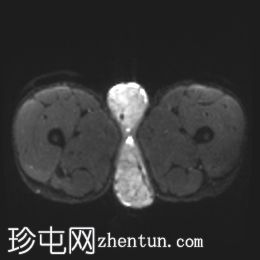

冠状位

T1加权像

2.jpg

阴囊内睾丸增大,T1加权像上可见分叶状软组织病变,呈中高信号,T2加权像上呈低信号。

轻度双侧鞘膜积液。